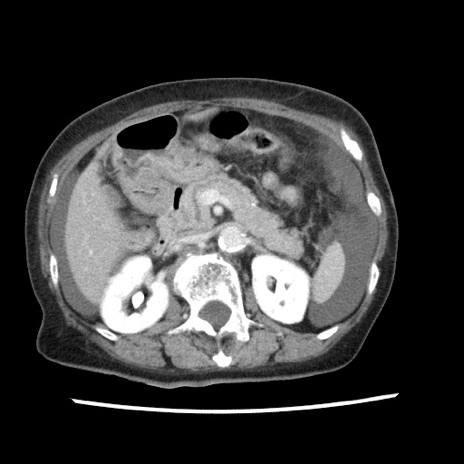

冠状断像

矢状断像

【症例】80歳代女性

【主訴】腹痛

【現病歴】8時間前から腹痛あり来院。

【既往歴】糖尿病、脂質異常症、子宮体癌にて子宮全摘術

【身体所見】意識清明・会話良好だが腹痛で苦悶様、全腹部にわたって反跳痛と圧痛あり

【データ】WBC 13600、CRP 0.14、LDH 224、CK 90